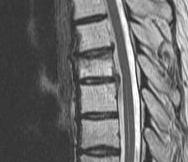

MRI

Very sensitive

- 40% incidence asymptomatic thoracic disc protrusion